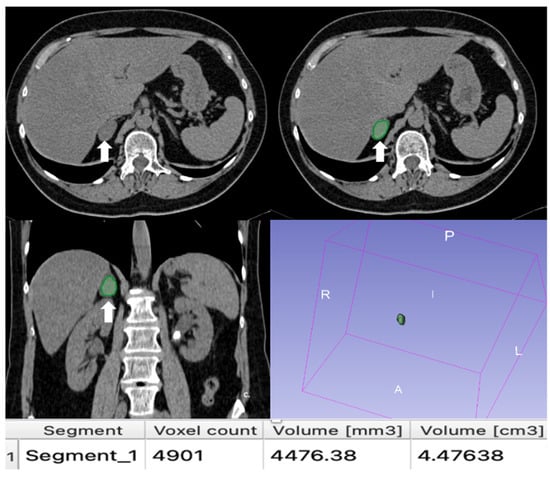

Figure 13.

An example of segmentation of an LPA in the right adrenal gland (arrow) in an unenhanced CT phase using 3D Slicer software (version 4.11). The volume of interest (VOI) of the LPA was manually drawn covering the whole lesion.